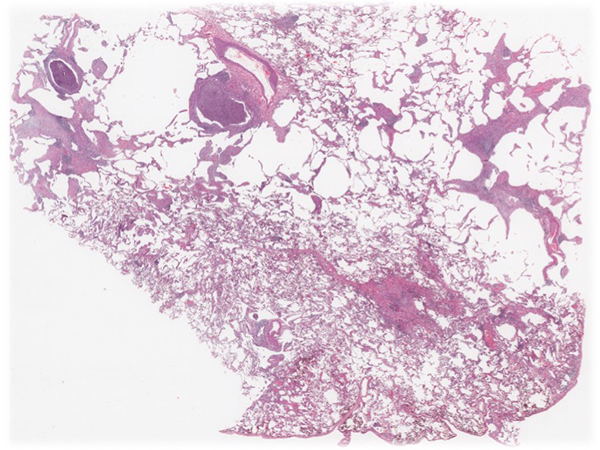

The natural clinical history comprises an early pre-vasculitic phase with overt allergic rhinitis, asthma (Figures 1 shows obstructive features comprising cellular bronchiolitis and luminal mucous plugs and figure 2 demonstrates classic features of asthma including moderate inflammation in the lamina propria and marked goblet cell hyperplasia), and blood and tissue eosinophilia, but no vasculitis clinically or in the biopsy; the vasculitic phase with eosinophilic-rich necrotizing or non-necrotizing vasculitis involving primarily small arteries (Figure 3 demonstrates necrotizing granulomatous vasculitis in small arteries), veins (Figure 4 shows venulitis) and capillaries (Figure 5 demonstrates capillaritis), granulomas and eosinophilic tissue infiltration (Figure 6). All these classic findings are not always actually found in the biopsy, particularly if the patient has been previously treated. In the postvasculitic phase in successfully treated patients the biopsy may show non-specific changes such as thrombosed small vessels in vessels with loss of the elastic layer.